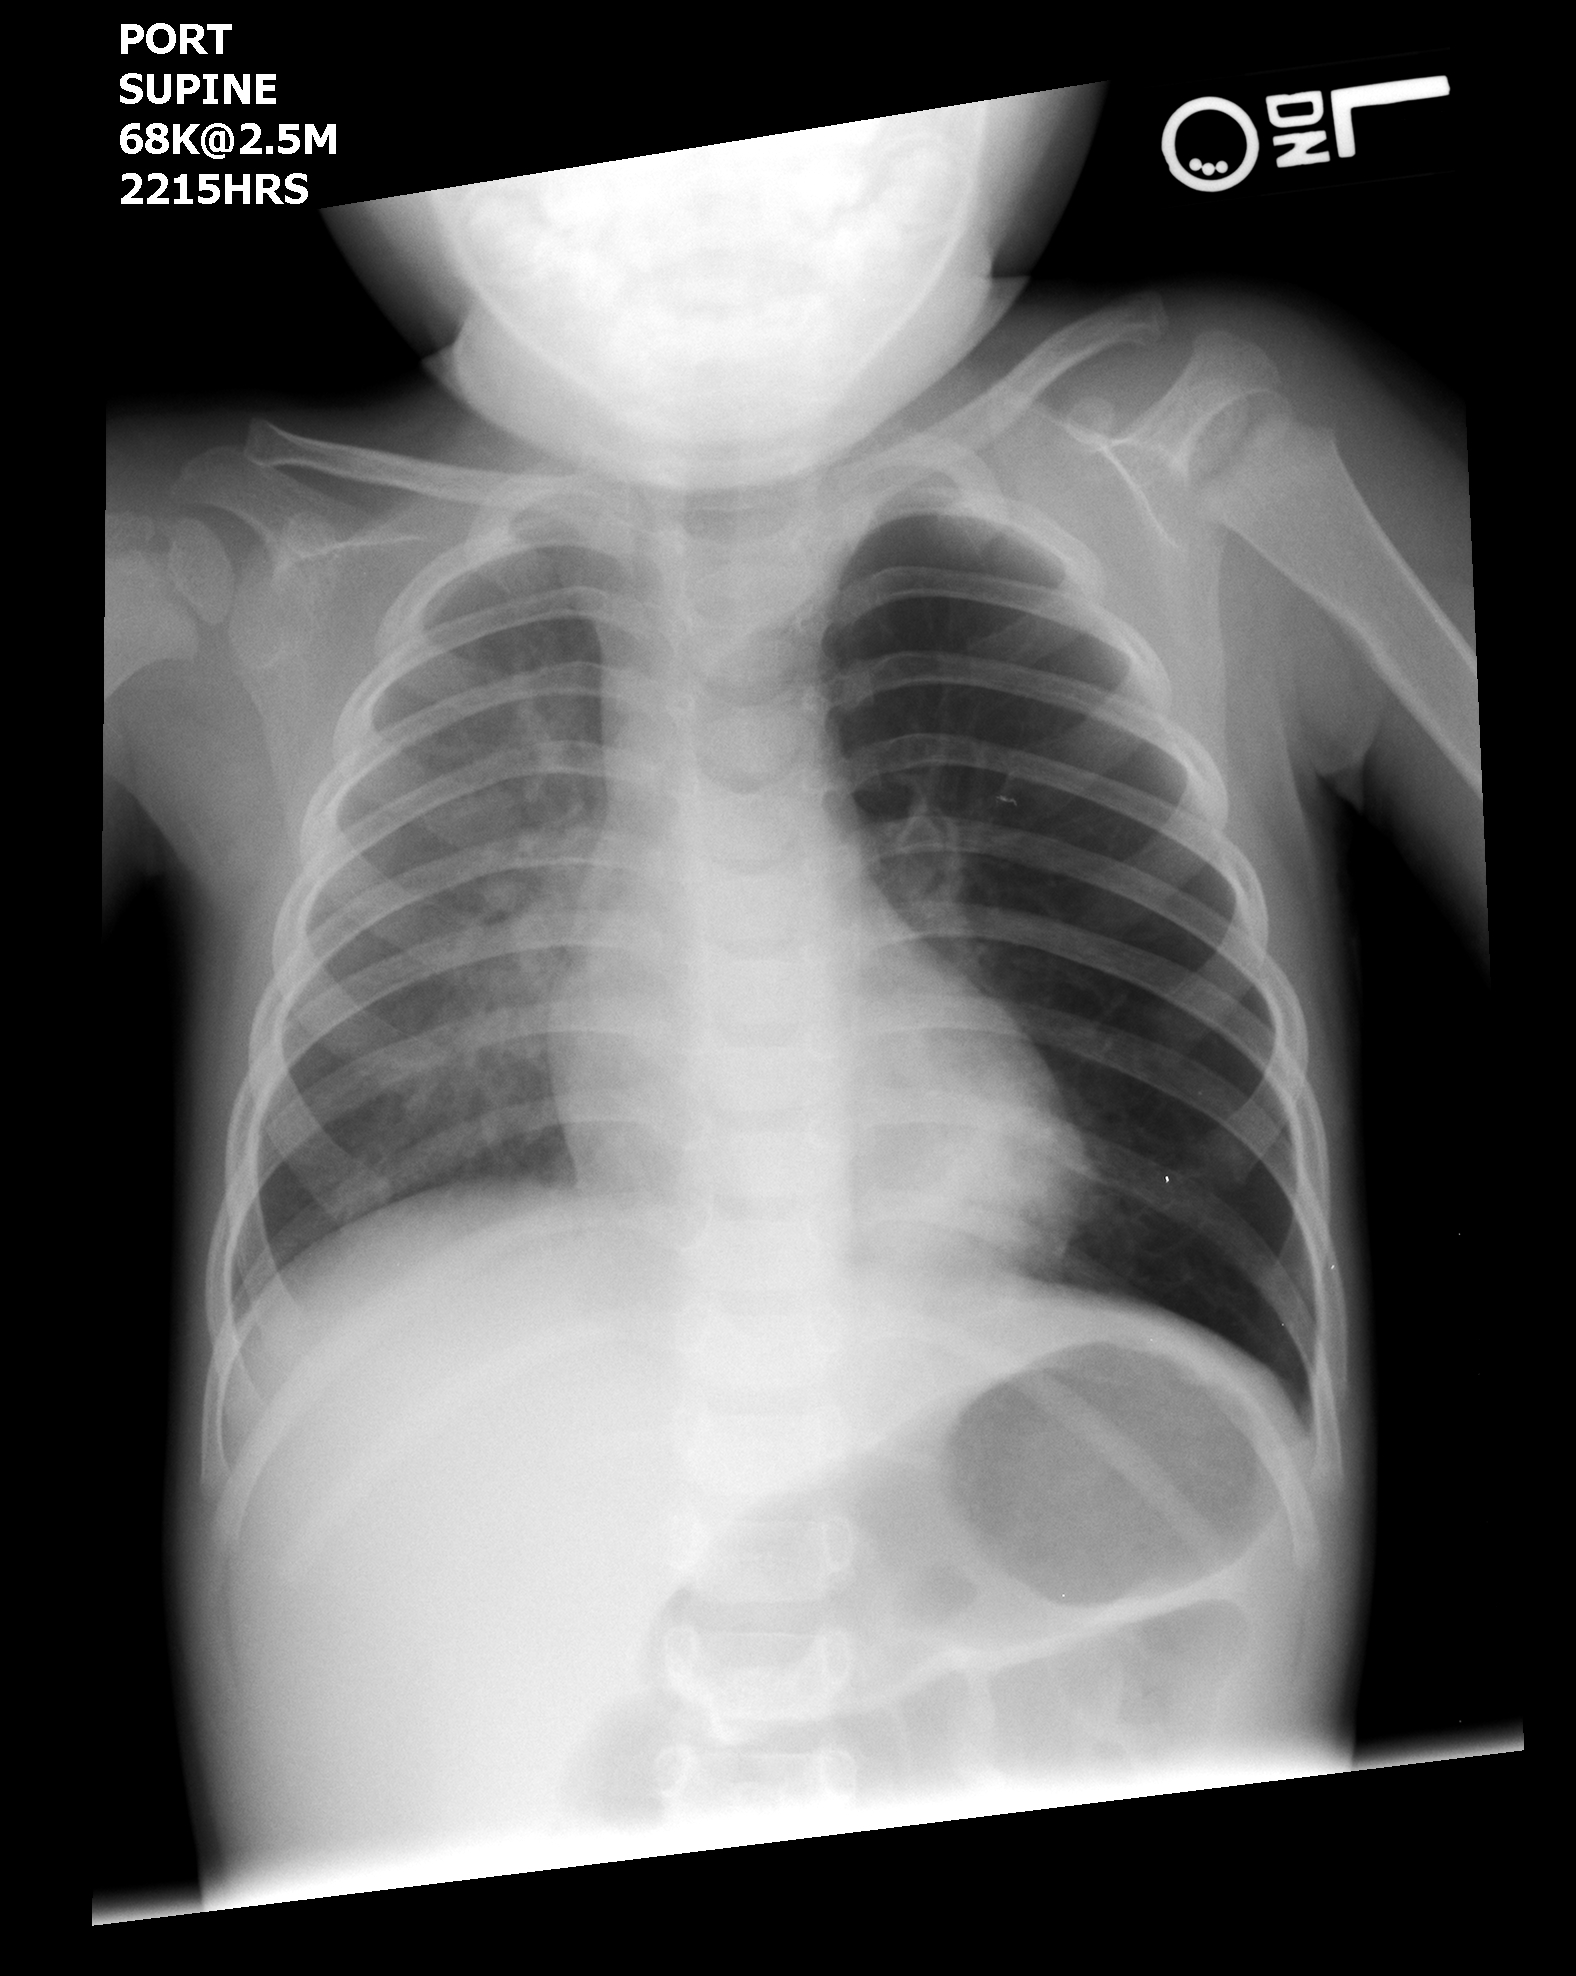

Нормальная рентгенограмма легких: что нужно знать

Раздел: Мудрость в объективе